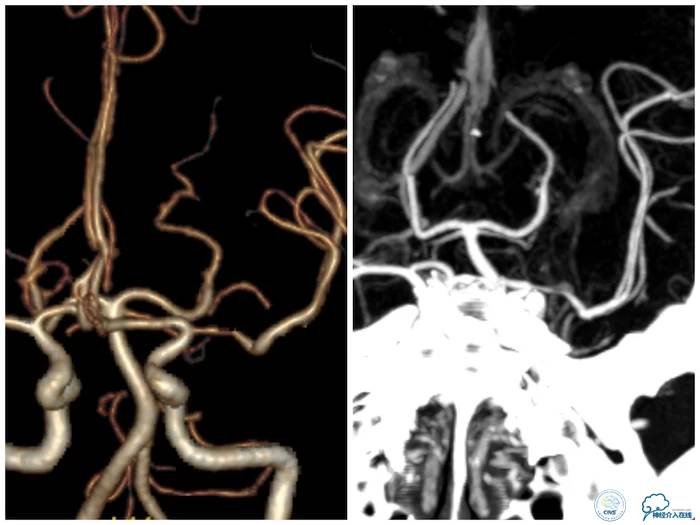

CTA:左大脑中动脉水平段狭窄(图5)。

图5